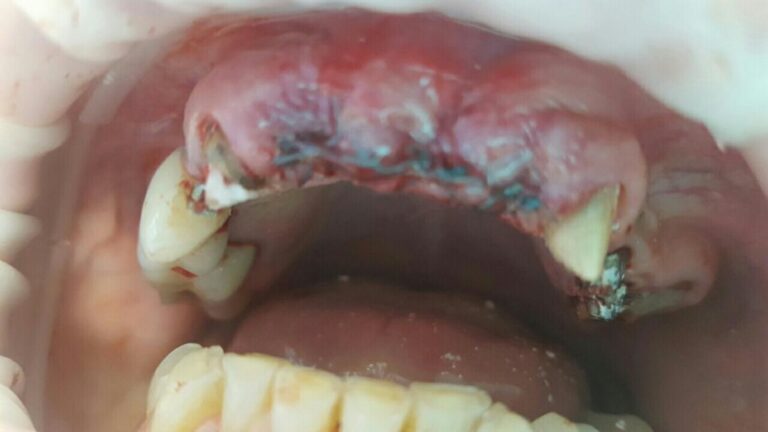

A patient case to the dental clinic with complaint connected with frond teeth defects. After the examination, he decided to provide dental treatment that includes immediate implantation of Alpha Dent implants. During the surgery he has placed 3 Alpha Dent implants in extracted teeth alveolar sockets. Then he placed allomaterial for bone regeneration over implants and sutured the wound.